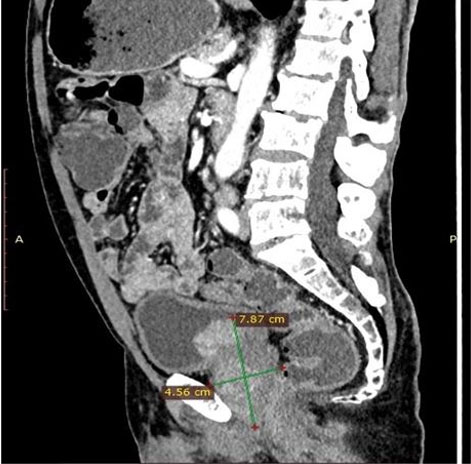

A 75-year-old male, African presented to the Uganda Cancer Institute (UCI), which is a tertiary cancer care facility in Uganda. The patient was a referral from a peripheral facility with a bladder mass, with a differential diagnosis of bladder cancer or prostate cancer given his age and presenting symptoms. Two months before referral, a partial transurethral resection of bladder tumor (TURBT) had been done, and the subsequent histology results were suggestive of fibrosarcoma, a diagnosis that was still queried by the primary clinician at the peripheral health facility. At UCI, the patient presented with a history of gross hematuria for one year, abdominal pain, dysuria, dribbling of urine, urgency and a feeling of incomplete voiding. A computed tomography scan of the pelvis done at UCI showed a residual tumor that was well-defined, and homogenous mass at the urinary bladder trigone, measuring 7.87 cm × 4.56 cm × 3.83 cm (Figure 1 and  Figure 2). The mass appeared to originate from the posterior bladder wall and not extending beyond the bladder wall, no infiltration into the seminal vesicles, and no enlarged lymph nodes seen the gastrointestinal tract was free of any involvement by the mass as per the imaging findings.

Figure 1: Abdominal CT scan images of the posterior bladder wall mass (black arrow).

Figure 2: CT scan images of the lateral view of the mass in greatest diameter.